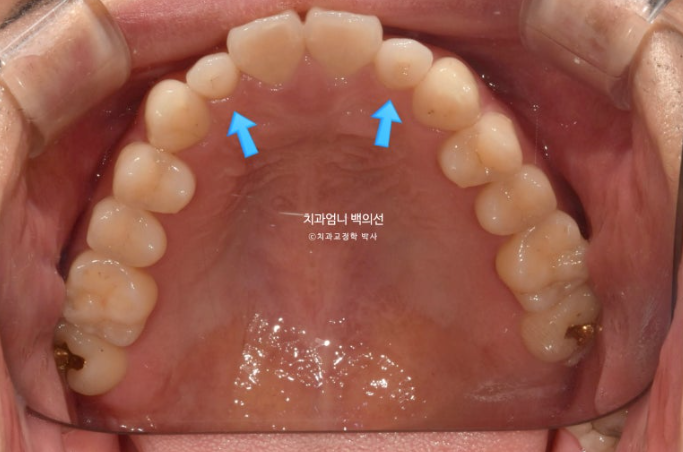

흰선 사이 작은어금니 하나가 결손상태이고 결손된 치아 쪽으로 주변 치아들이 쓰러져 있습니다.

파란화살표 측절치는 정상보다 작습니다.

파란화살표에 작은어금니 하나가 없습니다.

24.01~25.06

결손된 작은어금니 쪽으로 쓰러져 있던 큰어금니는 잘 세워졌습니다.

배열도 좋습니다